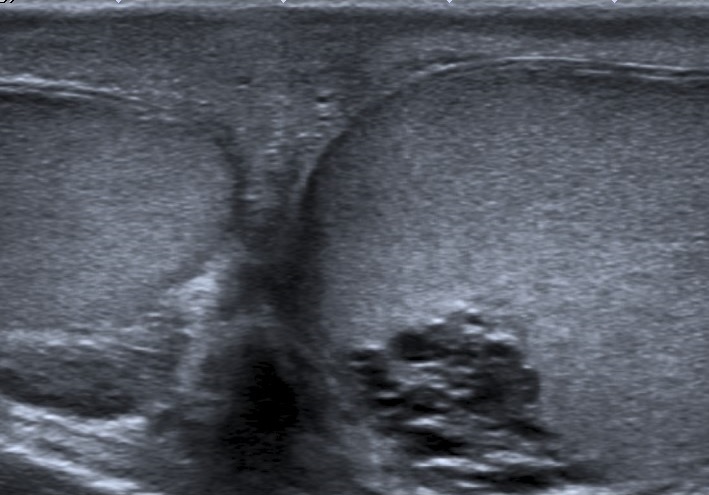

• Se realiza estudio con sonda lineal de alta frecuencia. Se explora el escroto y ambos testículos (figura 1), que presentan tamaño, morfología y ecoestructura normal, así como correcto flujo Doppler (figura 2). A nivel del teste izquierdo, se observa una colección de pequeñas imágenes anecoicas en el mediastino testicular, pseudotubulares. Además, una imagen anecoica, redondeada, quística, a nivel de la cabeza del epidídimo (figura 3).

• Se solicita ecografía testicular reglada que es informada como ectasia tubular de la rete testis en probable relación con antecedente de vasectomía y en la que se visualiza quiste de epidídimo izquierdo de 15 x 8 mm e hidrocele grado I, sin varicocele asociado.